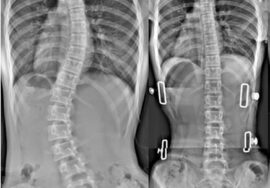

يُعد اعوجاج العمود الفقري عند المراهقين (الجنف) من أكثر مشكلات الظهر شيوعًا خلال فترة النمو. ورغم كثرة الأبحاث، لا تزال أسبابه الدقيقة غير مفهومة بالكامل. تشير دراسات حديثة إلى أن الغضاريف الموجودة بين فقرات الظهر قد تلعب دورًا مهمًا في بداية الاعوجاج أو زيادته.

أراد الباحثون معرفة ما إذا كانت الغضاريف بين فقرات أسفل الظهر تختلف عند المراهقين المصابين بالاعوجاج عن أقرانهم الأصحاء. كما سعوا لمعرفة هل هذه التغيرات سبب لظهور الانحناء أم نتيجة له مع مرور الوقت.

تم تصوير أسفل الظهر باستخدام جهاز الرنين المغناطيسي (MRI) للحصول على صور دقيقة لجميع الغضاريف.

ثم حلل الأطباء الصور لمعرفة:

شكل الغضاريف واتجاه ميلها.

موقع الجزء اللين في وسط الغضروف (النواة).

مدى تماثل الغضروف بين الجانبين الأيمن والأيسر.

كما تمت مقارنة النتائج مع درجة ميل الفقرات أو ما يُعرف بـ”زاوية الانحناء”.

وُجد أن الغضاريف عند المصابين تميل نحو الجانب الخارجي من الانحناء، حيث يتحرك مركز الغضروف من المنتصف باتجاه هذا الجانب.

هناك علاقة مباشرة بين زيادة درجة الانحناء وبين زيادة انحراف الغضروف. أي أن الاعوجاج مع الوقت يجعل الغضاريف أكثر ميلًا وعدم توازن.الضغط غير المتوازن هو السبب:

أثبتت الدراسة أن الغضاريف بين فقرات أسفل الظهر لدى المراهقين المصابين بالاعوجاج تميل نحو الجانب المقوّس من العمود الفقري، خصوصًا مع زيادة درجة الانحناء.